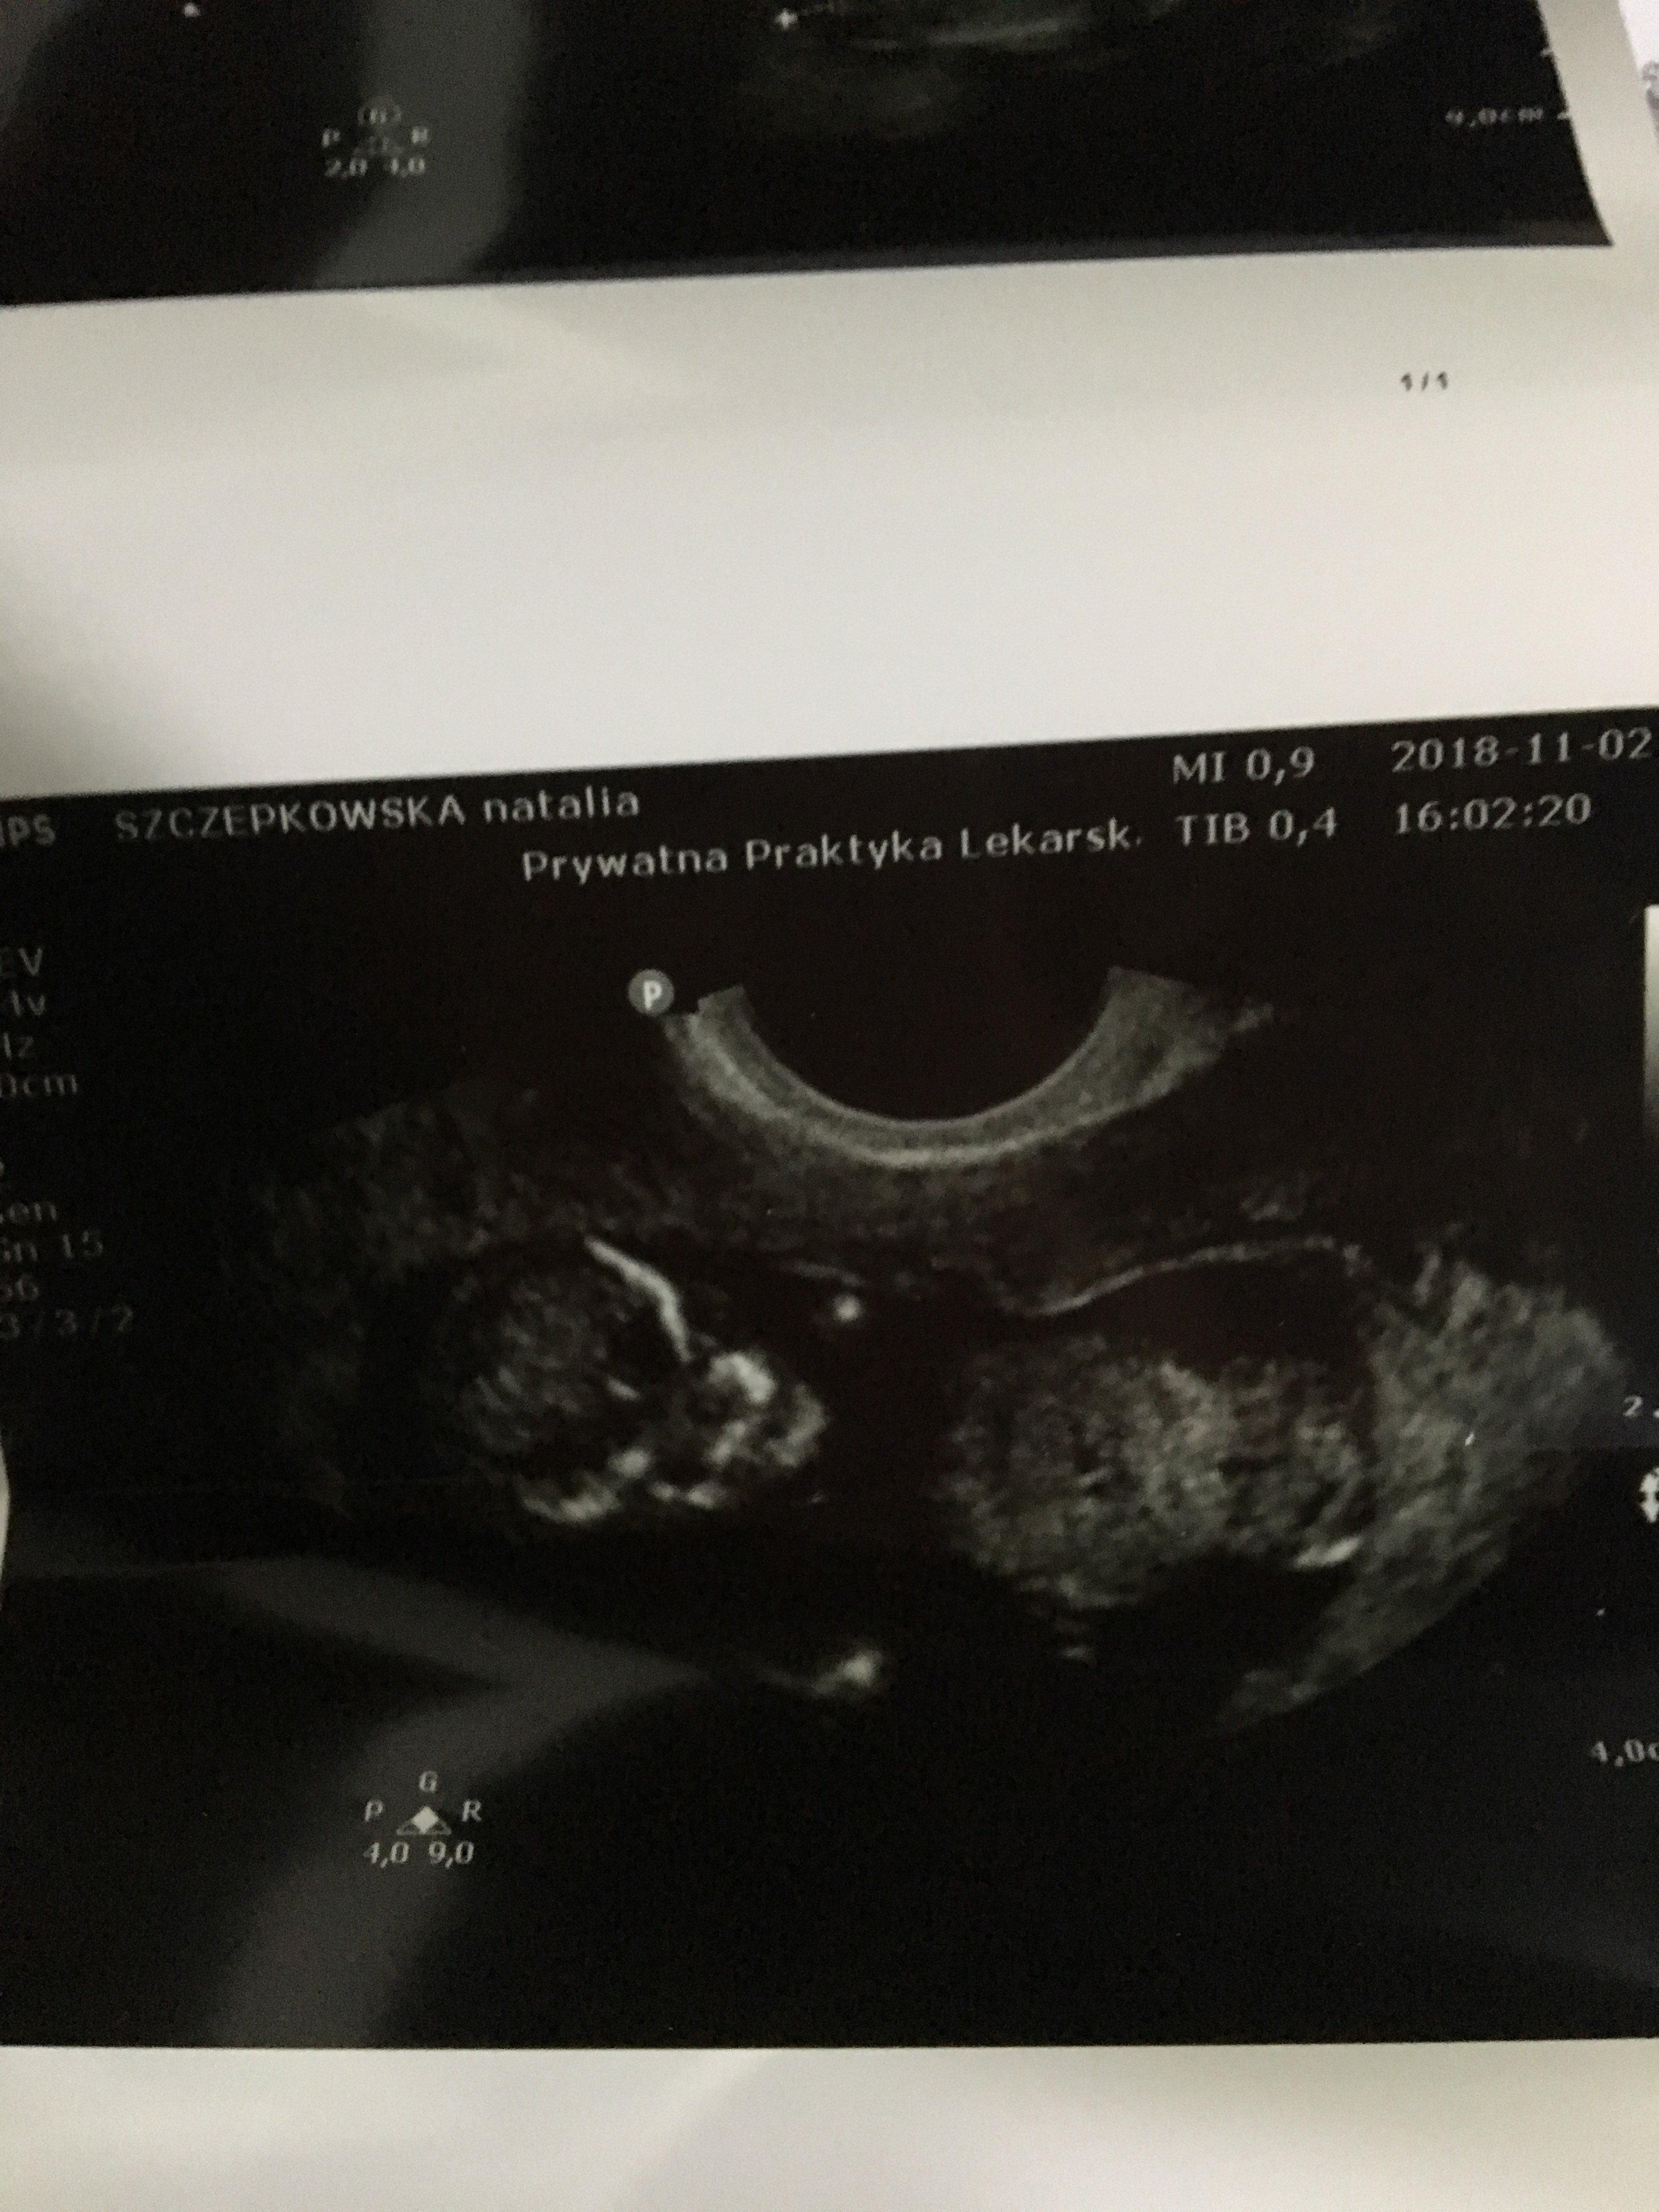

Witam w 19 tygodniu ciąży dowiedziałam się ze będę miała dziewczynkę w 20 tyg okazało się jednak , że to chłopak. Sama już nie wiem bo na jednym usg widać na pewno dziewuche a na drugim chłopca. Może to pempowina ?? Może ktoś mi pomoże rozwiązać ta zagadkę

no nic , zobaczymy na kolejnym USG. To doswiadczona Pani wiec chyba wie co mówi a ja ogladam zdjęcia pod każdym kątem i szukam śladów kobiecych